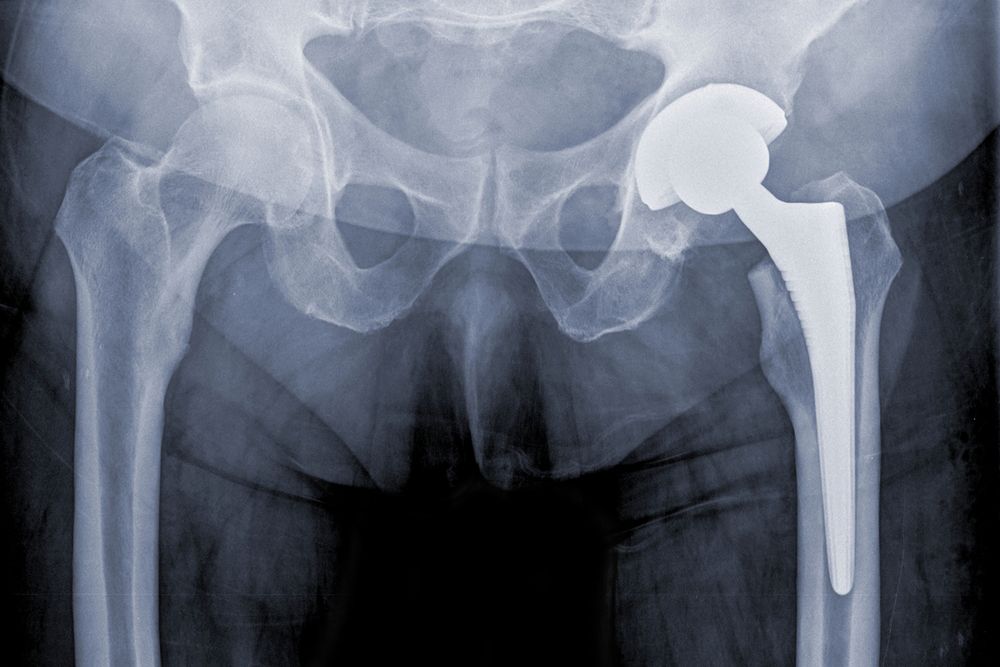

Medical devices can range from those that are implanted into our bodies, such as hip replacement systems, to those that we use externally, such as wheelchairs. Some of the more common medical devices to experience defects include:

- Hip replacement systems

Defective medical devices, particularly those that are implanted internally, can cause serious damage. Implants such as hip replacement systems and IVC filters can break and the pieces can migrate. This can cause damage to the internal organs. Other devices, like medical blankets, can harbor bacteria that can lead to serious infection. Still other devices, like a faulty wheelchair, can cause head injuries or broken bones. In the most severe of cases, injuries caused by a defective medical device can be fatal.

Defective medical devices, particularly those that are implanted internally, can cause serious damage.